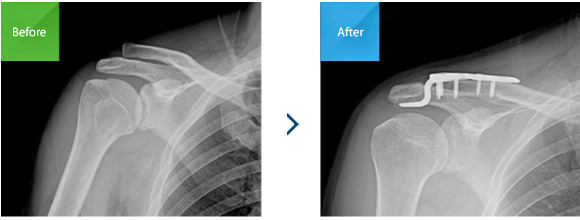

견봉-쇄골인대, 오구-쇄골인대에 파열이 일어났을 때 손상의 정도가 심하거나 운동선수와 같이 팔을 주로 쓰는 직업의 환자인 경우 시행하는 수술방법입니다.

갈고리(hook) 모양의 금속판과 나사를 이용하여

고정하는 방법